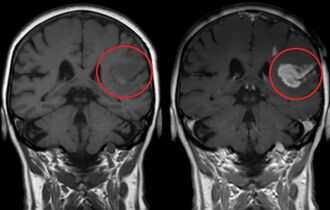

- МРТ черепных нервов позволят обнаружить защемление нервов, опухоли или другие аномалии, влияющие на функцию тройничного нерва. МРТ может выявить вазо-невральный конфликт, который, как полагают, вызывает боль при тройничной невралгии. Чувствительность и селективность МРТ, однако, в целом не может подтвердить или опровергнуть определенную нервно-сосудистую компрессию. Таким образом, наиболее важным аспектом в диагностике являются точные анамнестические сведения.